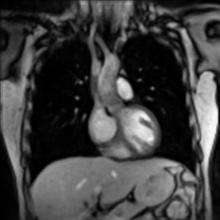

Cardiovascular

Cardiac MRI is complementary to other imaging techniques, such as echocardiography, cardiac CT and nuclear medicine. Its applications include assessment of myocardial ischemia and viability, cardiomyopathies, myocarditis, iron overload, vascular diseases and congenital heart disease.[23]